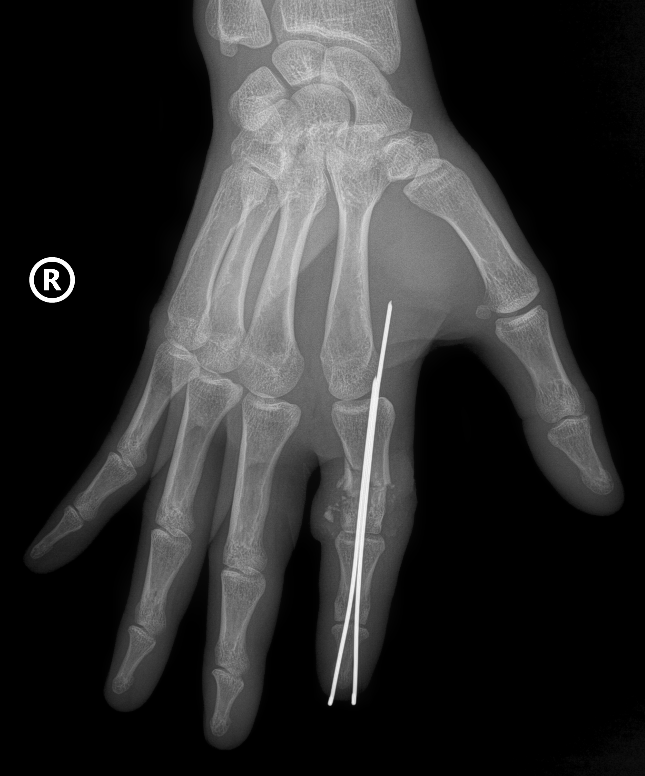

Hình ảnh X-Quang phần ngón trỏ tay phải bị đứt rời của anh D được định vị và cố định bằng kim chuyên dụng

Tại phòng mổ, kíp phẫu thuật cấp cứu được triển khai với sự phối hợp đa chuyên khoa: vi phẫu tạo hình, gây mê hồi sức, chấn thương chỉnh hình… Hai kíp phẫu thuật được triển khai song song, một kíp làm sạch và chuẩn bị phần ngón đứt rời, kíp còn lại chuẩn bị phần mỏm cụt. Xương ngón được định vị và cố định bằng kim chuyên dụng để tạo trục vững, hệ thống gân và dây chằng được phục hồi. Đặc biệt là thần kinh và các mạch máu nhỏ li ti chỉ khoảng 0,8 – 1mm được phục hồi với độ chính xác cao dưới kính hiển vi phẫu thuật với dụng cụ đặc biệt nhằm đảm bảo phục hồi lưu thông tưới máu cho phần đứt rời.